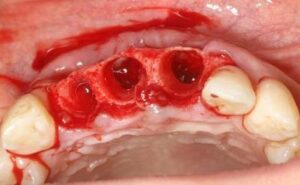

前歯3本欠損症例

前歯3本欠損症例 BEFORE AFTER 46歳女性/上3本欠損/インプラント埋込手術 【治療内容】 前歯3本に根尖病…